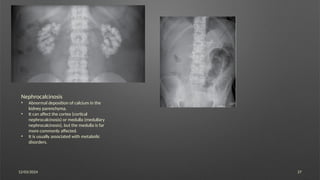

Nephrocalcinosis

• Abnormal deposition of calcium in the

kidney parenchyma.

• It can affect the cortex (cortical

nephrocalcinosis) or medulla (medullary

nephrocalcinosis), but the medulla is far

more commonly affected.

• It is usually associated with metabolic

disorders.